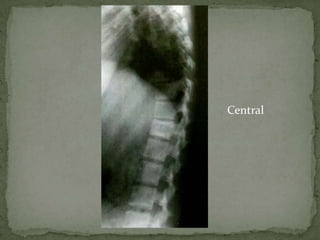

Central –

 Lytic area with absence of normal trabeculae in the

central portion

 Gradually enlarges

 Vertebral body may expand or balloon out like a tumor

 In later stages concentric collapse occurs, almost

resembling a vertebra plana

 Paravertebral shadows may be absent or minimal

 The disk space is either not affected or only minimally

affected

Central